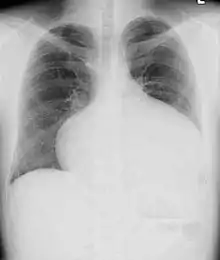

Adults with an uncorrected ASD present with symptoms of dyspnea on exertion (shortness of breath with minimal exercise), congestive heart failure, or cerebrovascular accident (stroke). They may be noted on routine testing to have an abnormal chest X-ray or an abnormal ECG and may have atrial fibrillation. If the ASD causes a left-to-right shunt, the pulmonary vasculature in both lungs may appear dilated on chest X-ray, due to the increase in pulmonary blood flow.[33]